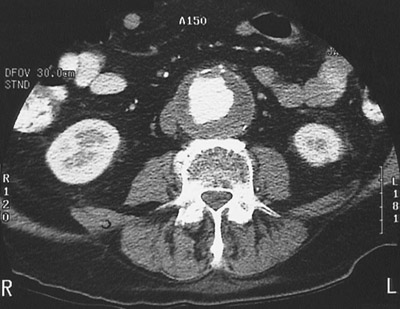

![]() | This abdominal high speed CT scan with contrast demonstrates an abdominal aortic aneurysm. Note the bright contrast material filling the lumen with surrounding mural thrombus that is darker. The total diameter is approximately 6 cm in diameter. At this size, there is increased risk for rupture. |